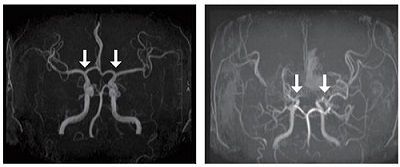

(사진 왼쪽부터 정상인 및 모야모야병 환자의 뇌혈관)